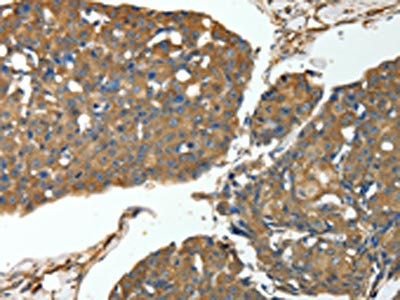

The image on the left is immunohistochemistry of paraffin-embedded Human ovarian cancer tissue using CSB-PA187078(MSN Antibody) at dilution 1/30, on the right is treated with fusion protein. (Original magnification: ×200)